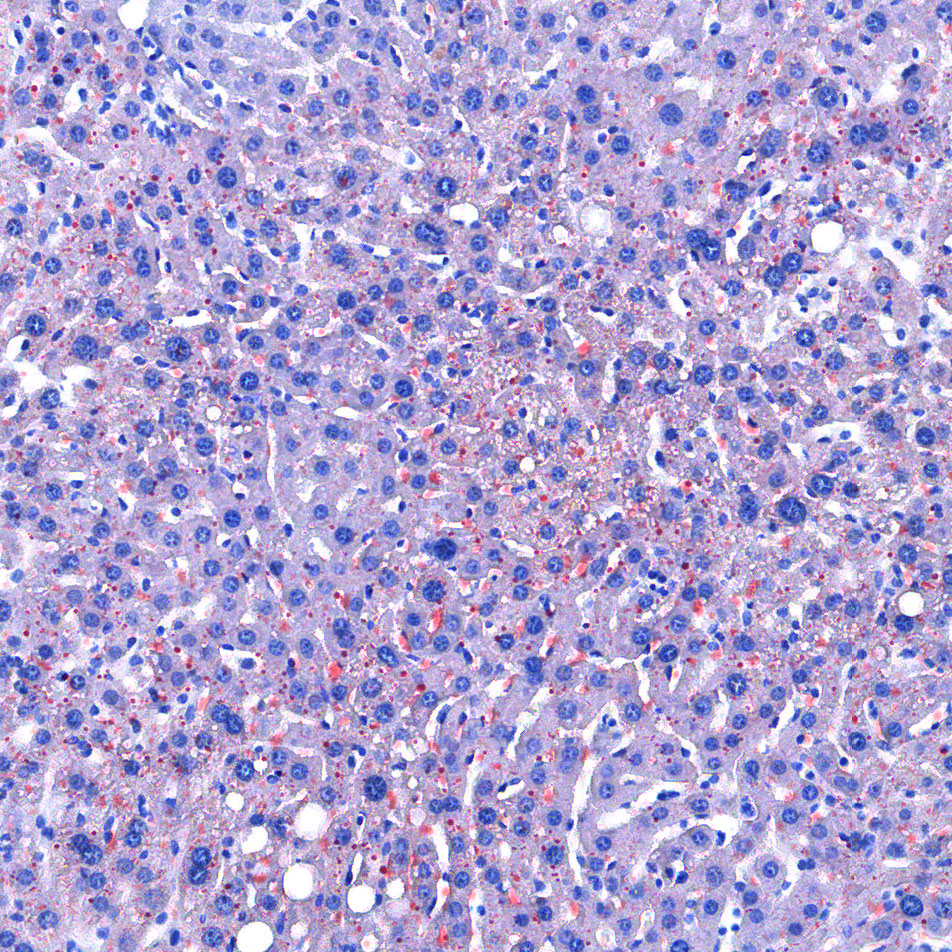

油红O染色

油红O对脂滴的染色机制一般认为是物理学上的溶液作用或吸附作用,借溶液作用使脂质染色,即油红O先溶于60%异丙醇中,然后切片浸入油红O染液中时,油红O在组织脂质的溶解度较60%异丙醇中的溶解度高,所以在染色时油红O从60%异丙醇中转移入脂质中使脂滴显示红色。

<油红O-肝>